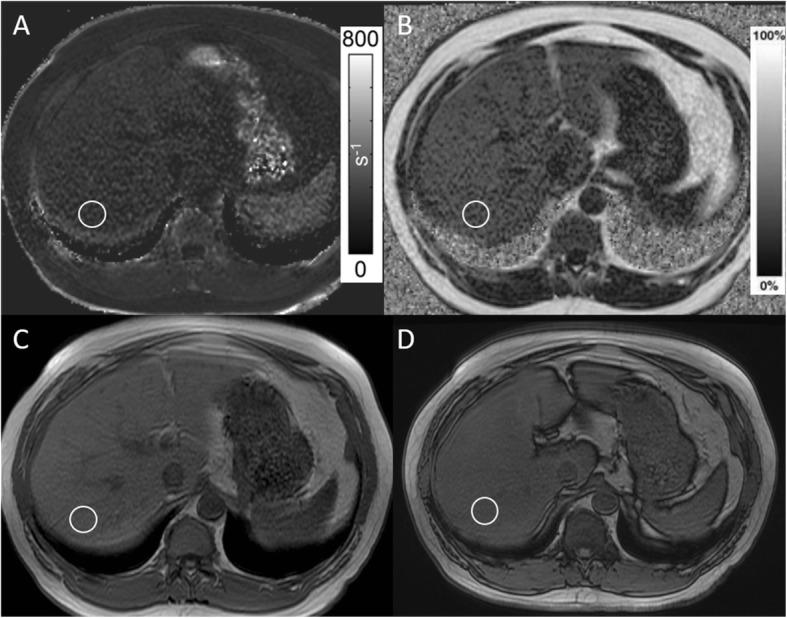

Cancer patients often have a history of chemotherapy, putting them at increased risk of liver toxicity and pancytopenia, leading to elevated liver fat and elevated liver iron respectively. T1-in-and-out-of-phase, the conventional MR technique for liver fat assessment, fails to detect elevated liver fat in the presence of concomitantly elevated liver iron. IDEAL-IQ is a more recently introduced MR fat quantification method that corrects for multiple confounding factors, including elevated liver iron.

This retrospective study was approved by the institutional review board with a waiver for informed consent. We reviewed the MRI studies of 50 cancer patients (30 males, 20 females, 50-78 years old) whose exams included (1) T1-in-and-out-of-phase, (2) IDEAL-IQ, and (3) T2* mapping. Two readers independently assessed fat and iron content from conventional and IDEAL-IQ MR methods. Intraclass correlation coefficient (ICC) was estimated to evaluate agreement between conventional MRI and IDEAL-IQ in measuring R2* level (a surrogate for iron level), and in measuring fat level. Agreement between the two readers was also assessed. Wilcoxon signed rank test was employed to compare iron level and fat fraction between conventional MRI and IDEAL-IQ.

RESULTS

Twenty percent of patients had both elevated liver iron and moderate/severe hepatic steatosis. Across all patients, there was high agreement between readers for IDEAL-IQ fat fraction (ICC = 0.957) and IDEAL R2* (ICC = 0.971) measurements, but lower agreement for conventional fat fraction measurements (ICC = 0.626). The fat fractions calculated with IOP were statistically significantly different from those calculated with IDEAL-IQ (reader 1: p < 0.001, reader 2: p < 0.001).

癌症患者通常有化疗史,这使他们有更高的肝毒性和全血细胞减少症风险,分别导致肝脂肪升高和肝铁升高。T1 同相位和反相位,这是常规的肝脂肪评估磁共振技术,在同时存在肝铁升高的情况下无法检测到肝脂肪升高。IDEAL-IQ 是一种最近引入的磁共振脂肪定量方法,可纠正多种混杂因素,包括肝铁升高。

本回顾性研究经机构审查委员会批准,豁免知情同意。我们回顾了 50 例癌症患者(30 名男性,20 名女性,50-78 岁)的 MRI 检查,这些检查包括(1)T1 同相位和反相位,(2)IDEAL-IQ,和(3)T2* 映射。两位读者分别从常规和 IDEAL-IQ 磁共振方法评估脂肪和铁含量。采用组内相关系数(ICC)评估常规 MRI 和 IDEAL-IQ 测量 R2*水平(铁水平的替代物)和测量脂肪水平的一致性。还评估了两位读者之间的一致性。采用 Wilcoxon 符号秩检验比较常规 MRI 和 IDEAL-IQ 之间的铁水平和脂肪分数。

结果

20%的患者同时存在肝铁升高和中重度肝脂肪变性。在所有患者中,读者对 IDEAL-IQ 脂肪分数(ICC=0.957)和 IDEAL R2*(ICC=0.971)测量的一致性较高,但对常规脂肪分数测量的一致性较低(ICC=0.626)。用 IOP 计算的脂肪分数与用 IDEAL-IQ 计算的脂肪分数有统计学差异(读者 1:p<0.001,读者 2:p<0.001)。